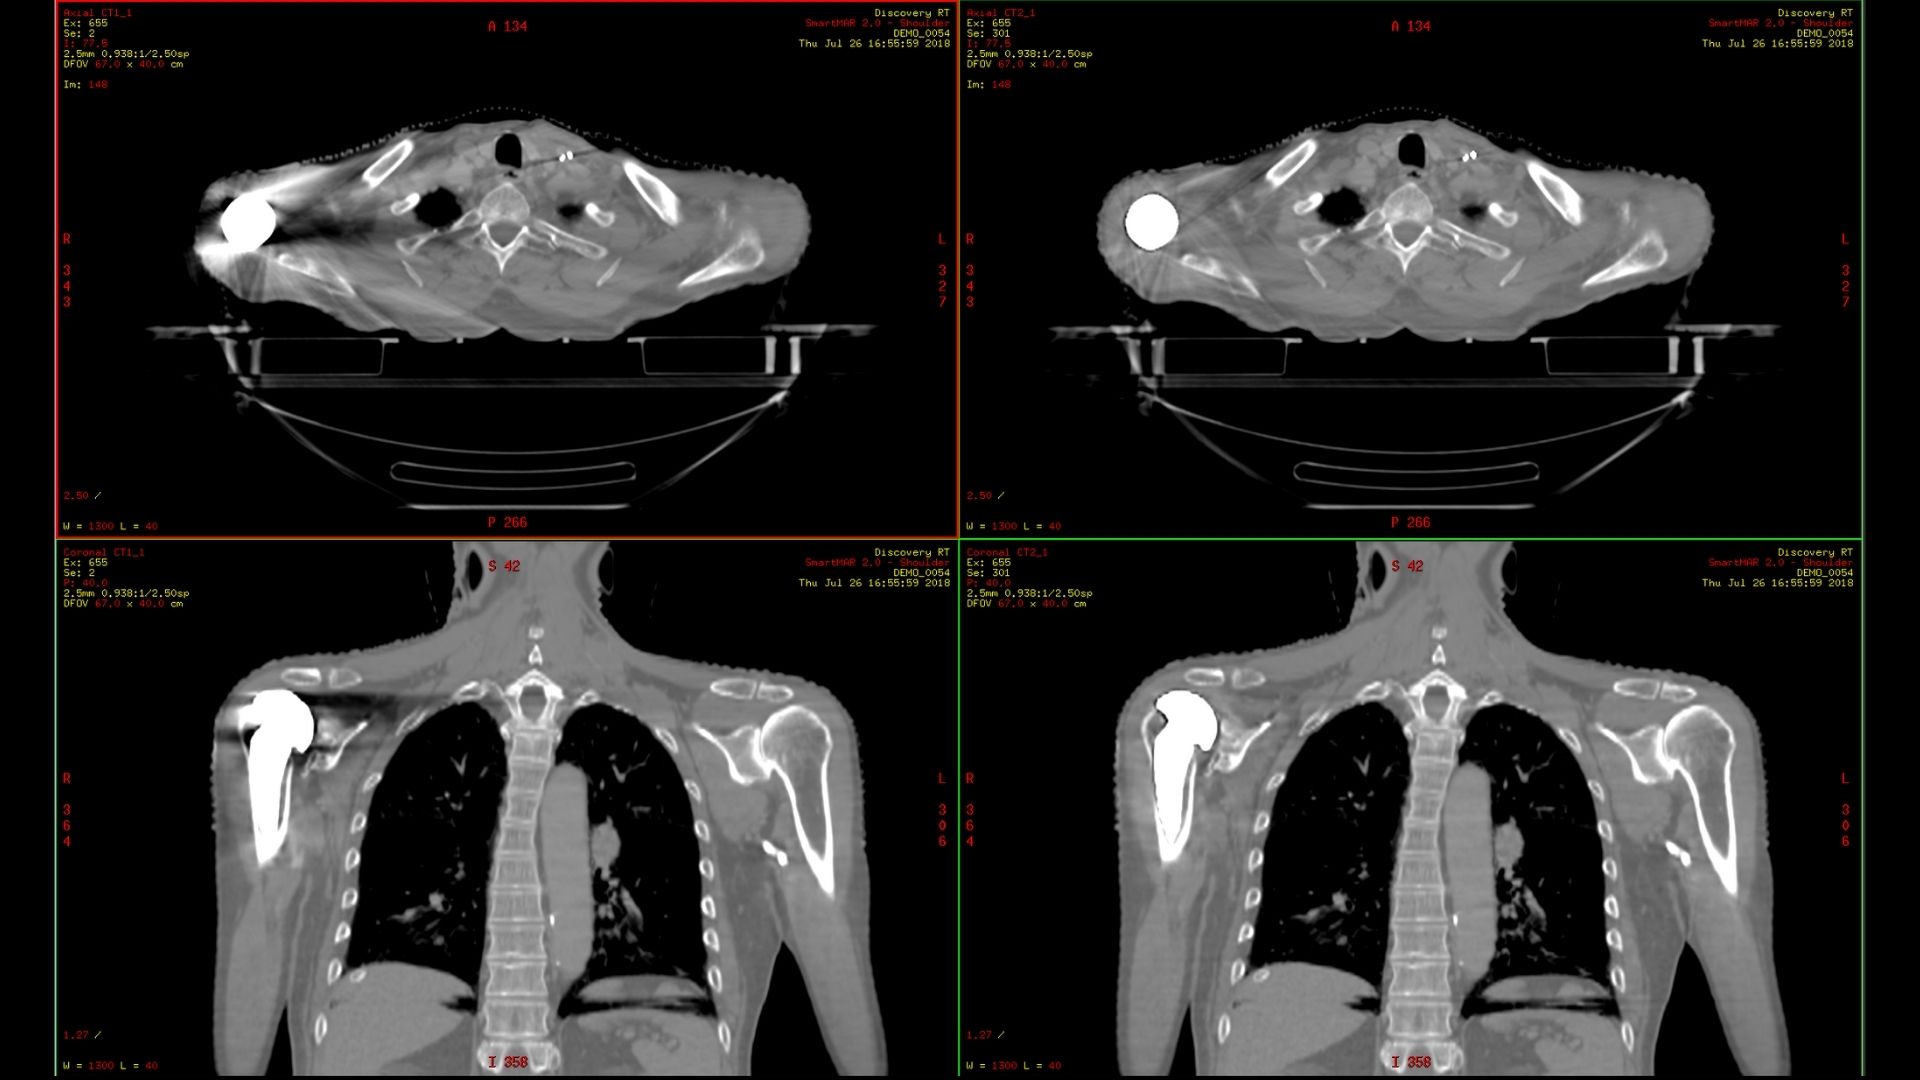

Construido sobre el éxito revolucionario de AIR™ Recon DL, nuestra primera innovación pionera en la reconstrucción de aprendizaje profundo, Sonic DL™ sigue con audacia sus pasos, avanzando en nuestra misión de revolucionar la RM. El aprendizaje profundo, cuando se aplica a la reducción del tiempo de exploración, convierte los minutos en segundos, lo que ofrece la rapidez de una TC y la calidad de una RM. Es mucho más rápido de lo que permiten las técnicas de aceleración convencionales actuales, lo que ayuda a los radiólogos a realizar diagnósticos precisos desde el principio.

Los departamentos de radiología llevan demasiado tiempo sobrecargados de trabajo. Los tiempos de exploración de RM más rápidos liberan más espacios de turnos y crean flujos de trabajo fáciles de gestionar. Ahora, con un solo ajuste, las configuraciones de la exploración pueden simplificarse. De este modo, se pueden ampliar las capacidades de todos los usuarios. Sonic DL™ está disponible tanto para sistemas 1,5 T y 3 T nuevos como antiguos.